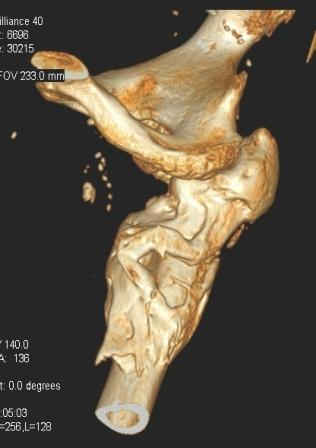

Уважаемый Глеб! Укорочение наверное побольше, да и наружно-ротационная установка скорее всего присутствует. Суставная щель прекрасная, головка живее всех живых. Ратую за подвертельную с латерализацией: исключает нарушение механической оси («исключает вальгус в коленe»), максимально удлиняет без натяжения m.iliacus. Для иллюстрации остеотомия-переделка (слава богу не автопеределка) у мужчины 65 лет.

PS. Извините за качество последнего снимка, рентгенограмма выполнена по м. жительства, там где был проведен синтез. Последний снимок выполнен через 2 мес. п\о, больной без разрешения начал наступать, слава богу все обошлось.